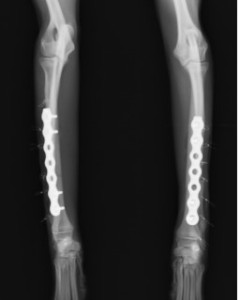

ロッキングプレートで整復しました。